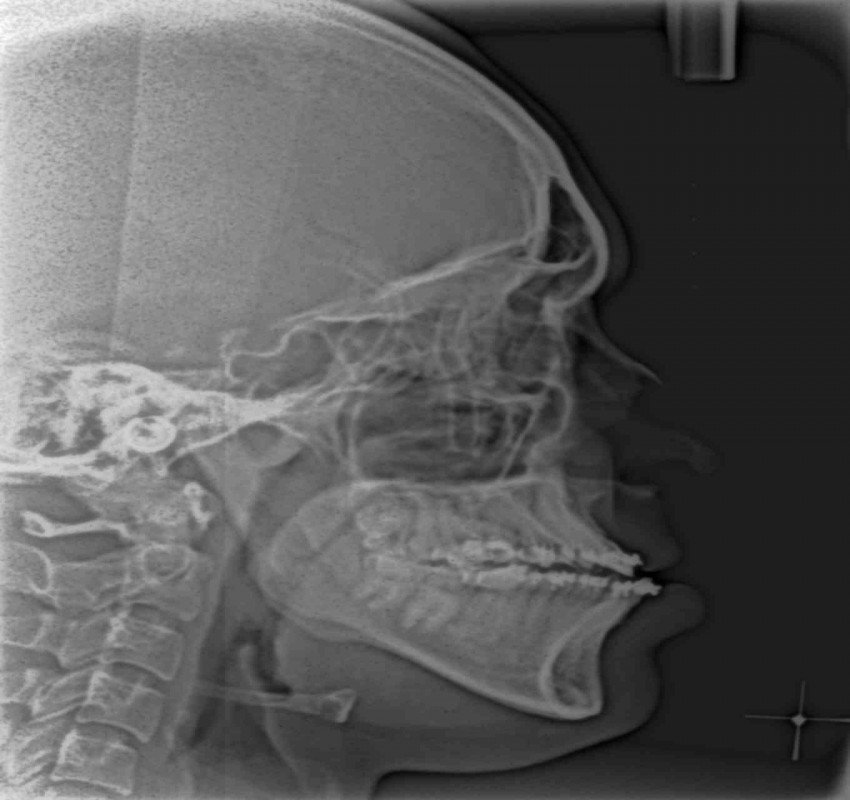

Dentistry has witnessed tremendous advances in all its branches over the past three decades. With these advances, the need for more precise diagnostic tools specially imaging methods has become mandatory. From the simple intraoral periapical x-rays, advanced imaging techniques like computed tomography, cone beam computed tomography, magnetic resonance imaging and ultrasound have also found their place in modern dentistry.

Changes from analouge to digital radiography has not only made the process simpler and faster but also made image storage and manipulation and retrieval easier. The 3- D imaging has made the complex craniofacial structures more accessible for examination.